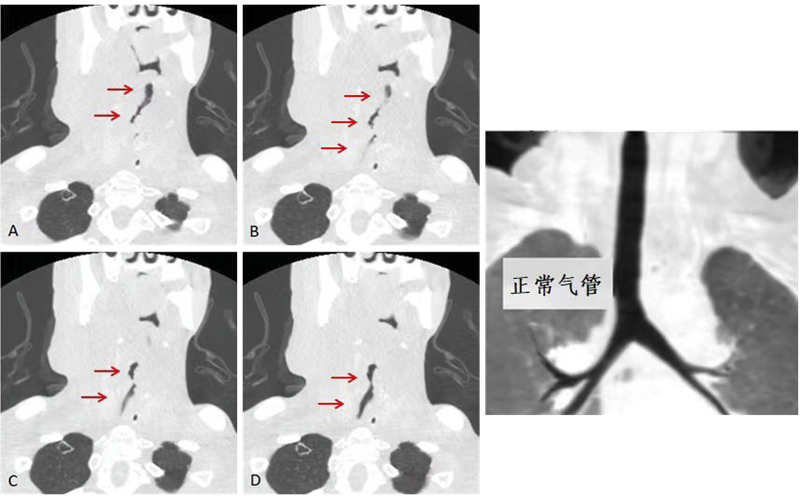

柳州市人民醫(yī)院的學科發(fā)展之路,是一條技術革新的探索之路。廣先生(化名)因呼吸困難到柳州市人民醫(yī)院就診,確診為喉癌術后復發(fā)及綜合治療后改變,已經(jīng)造成IV度喉梗阻,情況緊急,需立即建立人工氣道。經(jīng)過多學科聯(lián)合全院大會診以及和家屬的充分溝通,決定選擇在ECMO技術支持保護下進行人工氣道建立術及局部組織腫瘤浸潤清除術。

這一技術能在患者接受麻醉、手術時確保心肺功能,且讓患者保留自主呼吸功能,促進術后盡早恢復下床活動,減少感染及靜脈血栓發(fā)生。醫(yī)院ECMO團隊15分鐘完成穿刺置管及成功轉(zhuǎn)機,隨后將患者送入手術室順利完成手術,術中出血量僅5ml。